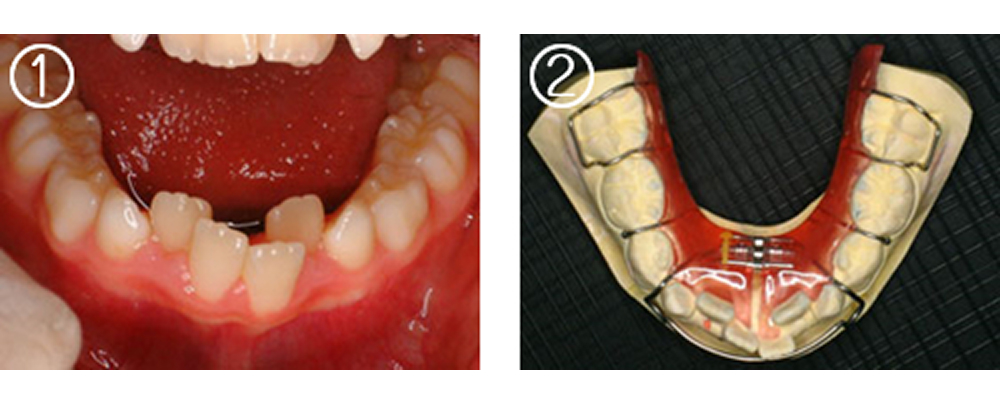

①術前 8歳 下顎4前歯の歯が並ぶスペースが不足。歯列弓も狭少

②拡大床を作製

③装着した所

④1年後スペースが確保され、歯列弓全体も拡大されている。ここまで広がれば,非抜歯で矯正できます